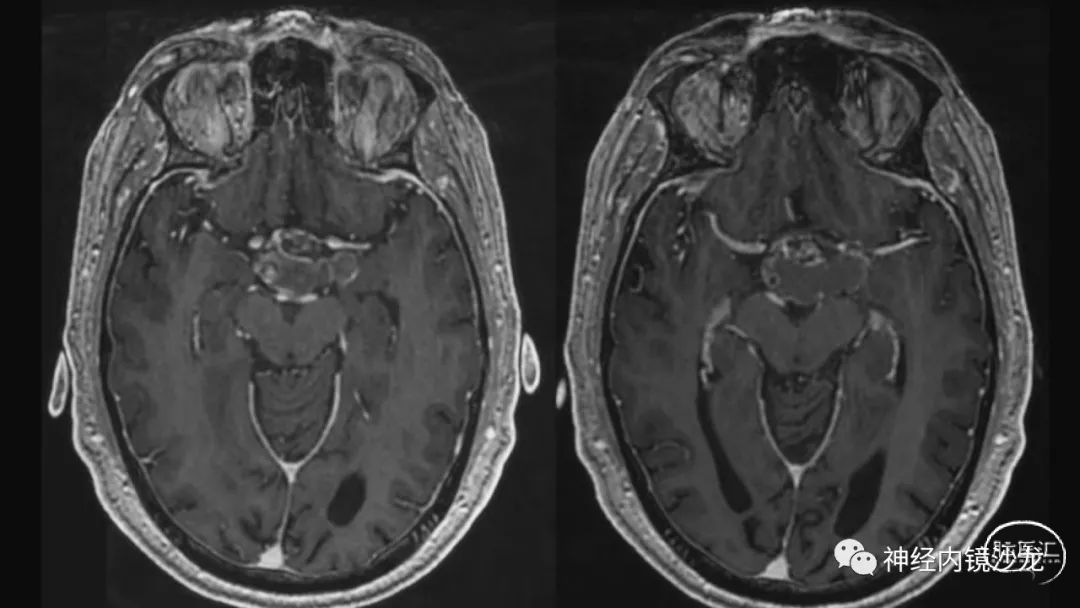

从事神经外科十余年,擅长神经外科肿瘤诊治,尤其是神经内镜微创手术治疗垂体瘤、颅咽管瘤、脑膜瘤等颅底肿瘤